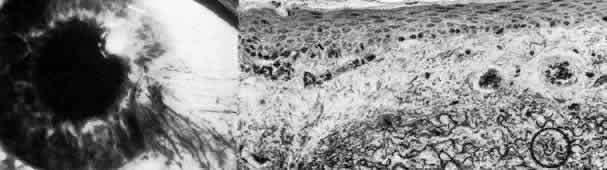

Reis-Bucklers Dystrophy

In 1917 Reis80 described a superficial corneal dystrophy that affected Bowman's layer, and in 1949 Bucklers81 noted an autosomal dominant mode of transmission in an additional family. The dystrophy is usually bilaterally symmetric and becomes evident in the first or second decade of life as painful recurrent erosive episodes. Patients develop decreased visual acuity due to anterior scarring and surface irregularity.

Slit lamp examination of the cornea shows an irregular epithelium with diffuse, irregular, patchy geographic opacities at the level of Bowman's layer (Figs. 5 AND 8). As time passes, central opacities develop as a reticulated pattern spreading into the midperiphery with a diffuse superficial stromal haze. Superficial keratectomy is helpful in managing the visual aspects of this disorder and should always be attempted before penetrating keratoplasty.82 Recurrence after keratoplasty has been described.83,84

Fig. 8. Reis-Bucklers dystrophy. Top left. Slit lamp photograph of eye of 26-year-old woman with recurrent erosions exhibits typical superficial reticular opacities. Top right. Phase-contrast microscopy demonstrates degeneration of dark-staining basal cells and fragmentation of Bowman's layer (*) by nodular fibrous pannus (paraphenylenediamine, × 800). Bottom. Transmission electron micrograph confirms thin remnants of disarrayed Bowman's layer (B) and apparent continuity (at arrowhead) between basal cell cytoplasm (E) and degenerate cellular debris (D) within Bowman's layer. Basement membrane complexes are discontinuous and lack anchoring fibrils (× 30,000).

The pathogenesis of Reis-Bucklers dystrophy is unknown. The primary lesion may be due to fragmentation of the collagen fibrils of Bowman's layer, and the epithelial lesion may occur secondarily.85 Alternatively, immunofluorescent localization of laminin and bullous pemphigoid antigen suggests a primarily epithelial disease.86 Destruction of Bowman's layer and its replacement by fibrillar material are the defining changes in this disease and unequivocally distinguish it from other anterior dystrophies. Concomitant abnormalities in the epithelial basement membrane account for recurrent erosive episodes.49,87–91